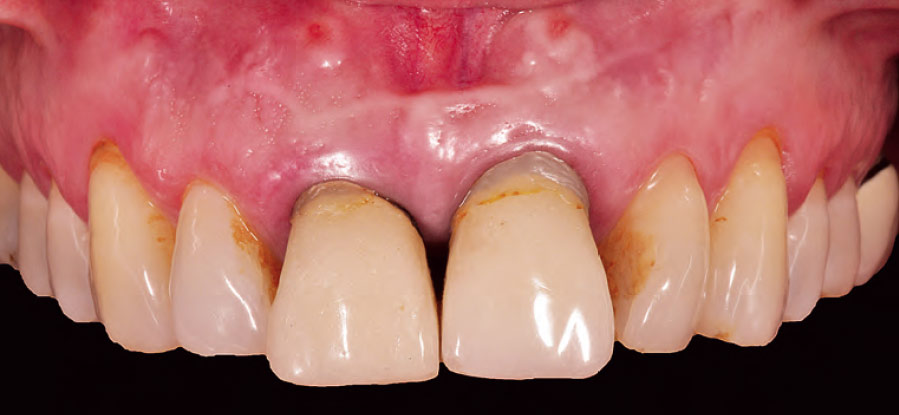

Si, infatti in ciascun capitolo sono presenti numerose immagini cliniche altamente esplicative

allo scopo di enfatizzare l'efficacia didattico-formativa del libro.

Nella gallery sotto alcune foto tratte dai capitoli del libro. Queste foto sono del prof. Eugenio Romeo